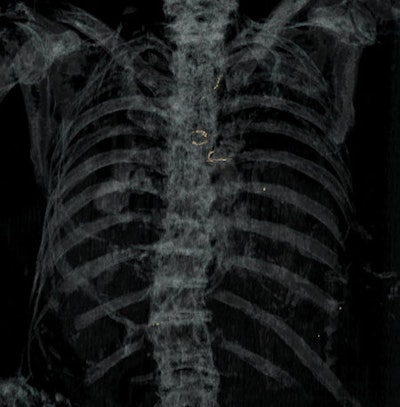

When a body is not identified or is unidentifiable -- as with skeletal, charred, putrefied, or mutilated individuals -- radiological investigation is necessary, and its major aims are identification of the person and of the injuries. This can be important in "hidden crimes" such as a person killed by gunshot and then burnt in their home. Comparison of antemortem radiographs or MSCT images with postmortem MSCT images can be vital for positive identification of the deceased: This is the goal of comparative identification, they explained.

In ballistic trauma, MSCT can help to determine criteria such as location of the projectile(s) and determination of the direction of fire plus entry and exit bone wounds. Ricochets may also be detected by imaging, and the same is true of sharp trauma, with visualization of deep bone laceration or of cartilage section in some cases.

"MSCT is effective in identifying infectious lesions, and is more informative than plain x-rays. Infectious processes can affect bones, teeth, and also soft tissues, so MSCT can be very helpful in study of mummies," the researchers noted. "More rarely, bone tumors may be observed, or features secondary to metabolic changes or anemia such as cribra orbitalia, Harris lines, osteopenia, or osteoporosis. Foreign bodies may also be detected within bones."